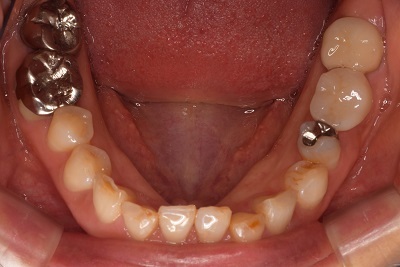

Step-1 CTデータ、X線撮影、模型診査による術前のシュミレーション

右上の親知らずを左下6番目に移植